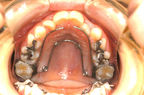

下顎前突(かがくぜんとつ)・受け口

主訴:受け口・前歯部交叉咬合

年齢:7y2m

診断:上顎劣成長による骨格性下顎前突

装置・期間:

第一期治療 上顎拡大+上顎前方牽引装置(クアッドヘリックス+フェイシャルマスク)+バイヘリックス+セクショナルアーチ 6年7カ月間(7y5m~14y0m)

第二期治療 上下顎マルチブラケット装置 3年5カ月間(16y2m~19y7m)

保定 上下顎保定装置 2年間以上

治療費:第一期治療 矯正基本料400,000円+処置料3,000~6,000円×40回(別途消費税)

第二期治療 矯正基本料400,000円+クリアブラケット代30,000円+処置料3,000~6,000円×37回(別途消費税)

保定装置料 55,000円(別途消費税)